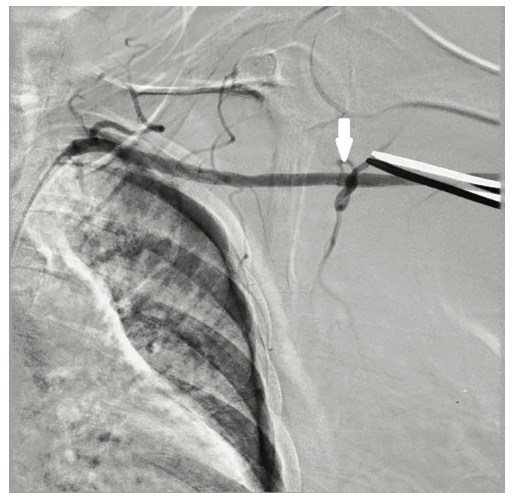

The right groin was accessed using fluoroscopic guidance. A micropuncture sheath was placed and upsized to a 7 French, 45 cm Destination sheath (Terumo) in the right groin. We accessed the right radial, but could not get good flow. Therefore, we ended up using the ulnar artery with ultrasound guidance and placed a Terumo 5/6 Slender sheath in the ulnar artery. We proceeded to access the left axillary artery. We placed a Judkins right (JR)4 catheter in the left subclavian and did a selective angiogram, documenting the location of the thoracoacromial artery and circumflex humeral (Figure 4); then using a Chiba biopsy needle (Cook), accessed the axillary artery and placed a 5-French 30 cm sheath (Cook)(Figure 5). We used the 15 cm biopsy needle to allow us a shallow angle of approach with the patient’s body habitus and to avoid “kinking” the sheath. We then switched out for the Lunderquist wire (Cook Medical), placed an 8 Fr sheath, and performed a pre-close using two Perclose devices (Abbott Vascular) (Figure 6).

Ideally, the axillary artery should be accessed in the second portion, which runs behind the pectoralis minor muscle. This is clinically important, since it is associated with the lowest chance of causing brachial plexus injury. These landmarks are often seen using ultrasound imaging. However, our practice is to use selective angiogram of the subclavian and axillary arteries. Once the axillary artery and all branches are defined, the access point should be lateral to the thoracoacromial artery and medial to the circumflex humeral arteries (Figures 22-23). We recommend a shallow angle of approach, since the Impella sheath is prone to kinking; alternatively, a Cook 14 Fr x 13 cm sheath can be used for the Impella 2.5 or a Cook 14 Fr x 30 cm sheath for the Impella CP.

- Angiographic assessment of the axillary artery and all branches is an important step to define an access point that is lateral to the thoracoacromial artery and medial to the circumflex humeral artery (Figures 22-23).